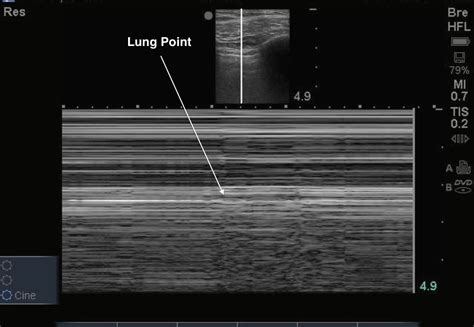

Lung point on motion mode (Mmode). The arrow indicates a transition

Lung Point Sign